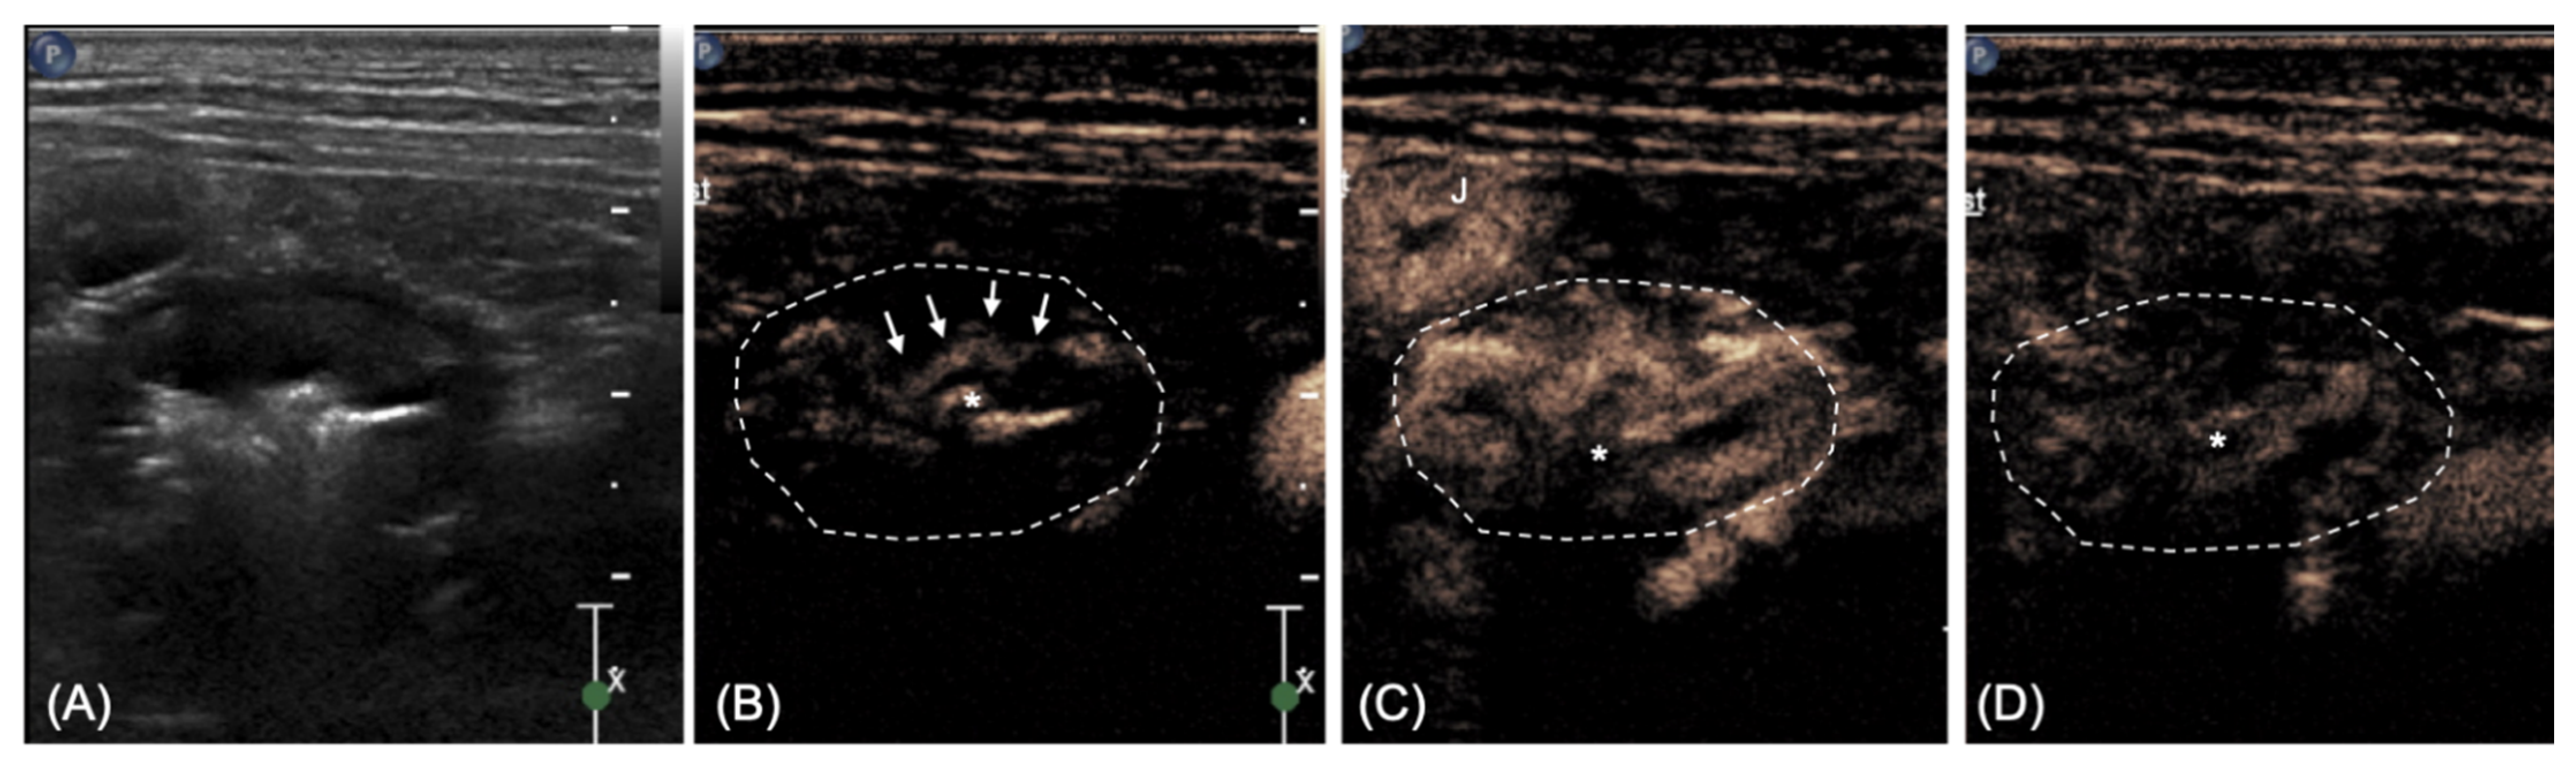

2.2. Imaging Diagnosis